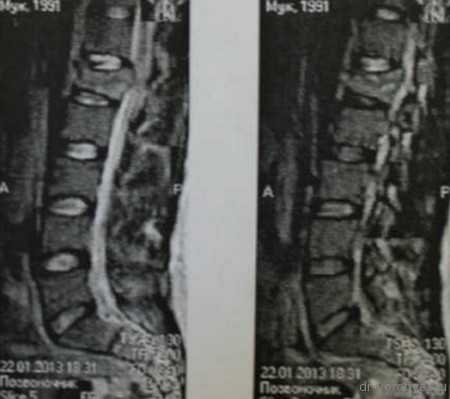

Первым этапом проведена корпорэктомия третьего поясничного позвонка и корпородез МЭШем, заполненным аутокостью

Вторым этапом, с целью создания ротационной стабильности, компрессии позвонков проведена транспедикулярная фиксация.